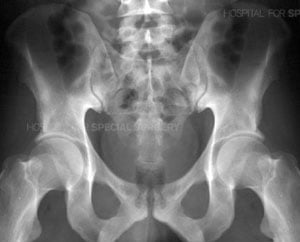

Radiograph of a normal pelvis